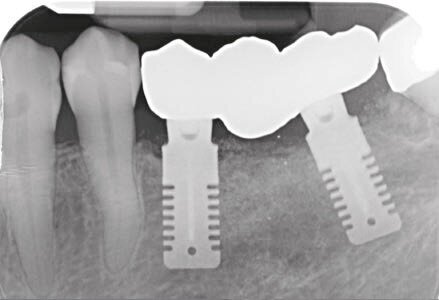

Dopo 6 mesi abbiamo effettuato delle Rx di controllo e misurato nuovamente il valore ISQ. Dopo aver riscontrato valori positivi abbiamo svitato le viti di guarigione e abbiamo avvitato gli specifici REXmarkers direttamente sugli impianti REX PiezoImplant. Abbiamo quindi effettuato un’impronta digitale con l’ausilio di uno scanner digitale Carestream 3600. Con l’esportazione dei file STL è stato possibile realizzare una protesi avvitata disegnata con Exocad*** che dispone al suo interno delle librerie protesiche REX PiezoImplant. È stato quindi consegnato il manufatto protesico definitivo che è stato avvitato a 25 N dopo aver controllato radiograficamente il corretto accoppiamento.

Fig. 16 - RX di accoppiamento.